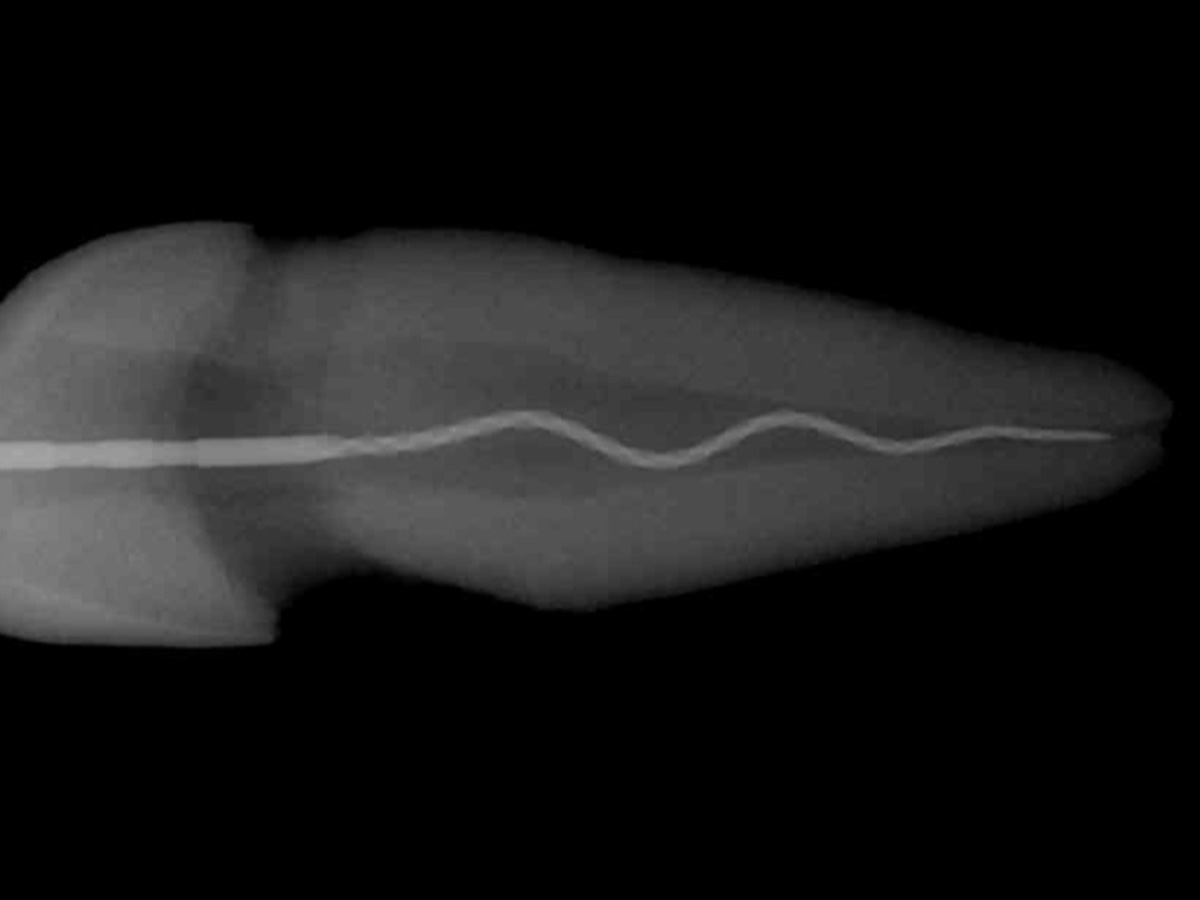

• Revisionsübung mit der XP-endo® Rise Feile

• Effektive Entfernung von Guttapercha